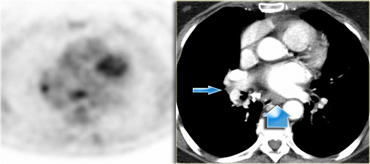

8. Hạch cạnh thực quản

Hạch ở dưới carina và kéo dài theo chiều dọc đến cơ hoành.

Hạch ở bên phải thực quản (nhóm 8).

Hình ảnh PET-CT cho thấy hấp thụ FDG ở hạch nhóm 8.

Trên hình ảnh CT cho thấy hạch không xâm lấn (mũi tên xanh).

Đây có thể là hạch di căn.